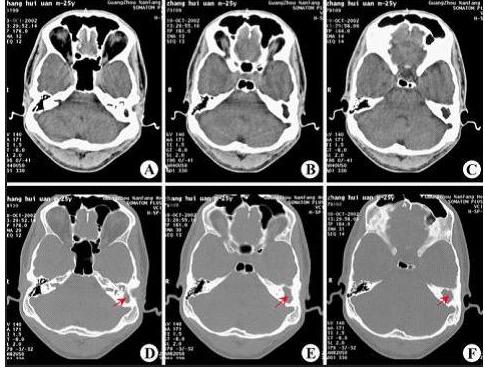

乳突炎常继发于中耳炎,引起乳突粘膜充血及水肿,分泌物增多。继续发展可破坏气房间隔,甚至破坏乳突骨壁...[详情]

乳突炎是乳突气房粘膜及骨质的急性化脓性炎症,多由急性化脓性中耳炎发展而来。据西安新城中大耳鼻喉医院...[详情]